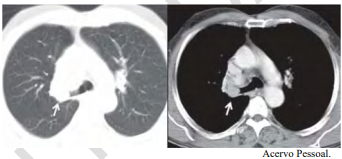

Uma paciente de 47 anos de idade, não tabagista, apresenta episódio de tosse e hemoptise. A tomografia computadorizada de tórax, realizada para investigação, evidenciou um nódulo pulmonar, com densidade de partes moles, de 2,1 cm, com obstrução do brônquio lobar superior direito, demonstrada nas imagens a seguir. Não há linfonodos mediastinais aumentados. A fibrobroncoscopia para investigação evidenciou uma lesão sólida em brônquio lobar superior direito, com obstrução total do brônquio, e aspecto em dedo de luva. As tomografias computadorizadas de abdome e de crânio não identificaram lesões metastáticas a distância. A biópsia endobrônquica demonstrou ser um carcinoide típico.